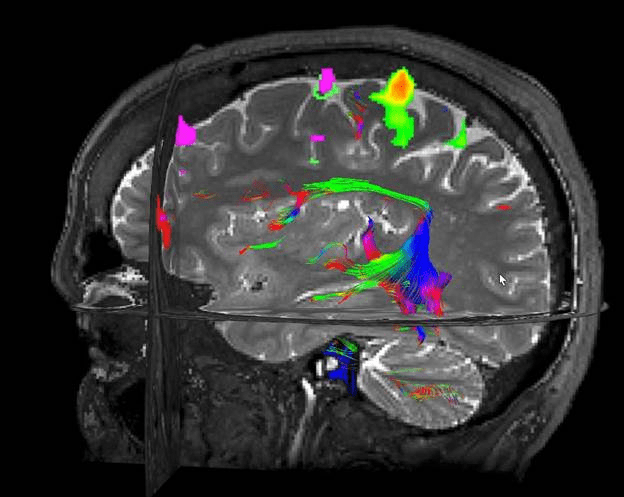

In this study, 19 volunteers underwent functional MRI testing of the brain (fMRI looks at real-time changes of blood flow in organs) to evaluate brain activity in the setting of color. By the way, a good review of the article is in Nature.

An image of fMRI from the University of Florida

In this study, male and female human subjects had fMRI readings of their brains performed while they looked at red, green, and yellow colors. Next, fMRI readings of their brains were repeated while they were asked to come up with mental images of these same colors.

Here is the fascinating part… The study authors performed mapping of retinotopically matched visual areas in association with these colors. This mapping determines the part of the brain being signaled when a part of the retina is observing colors. They found that the specific area of the brain known as human visual area 4 (or hv4) had an extremely high correlation in brain activity as seen in fMRI when patients were shown colors or when they thought about colors. This hv4 area signalled the same whether study subjects 1) saw specific colors or 2) thought about the same specific colors.